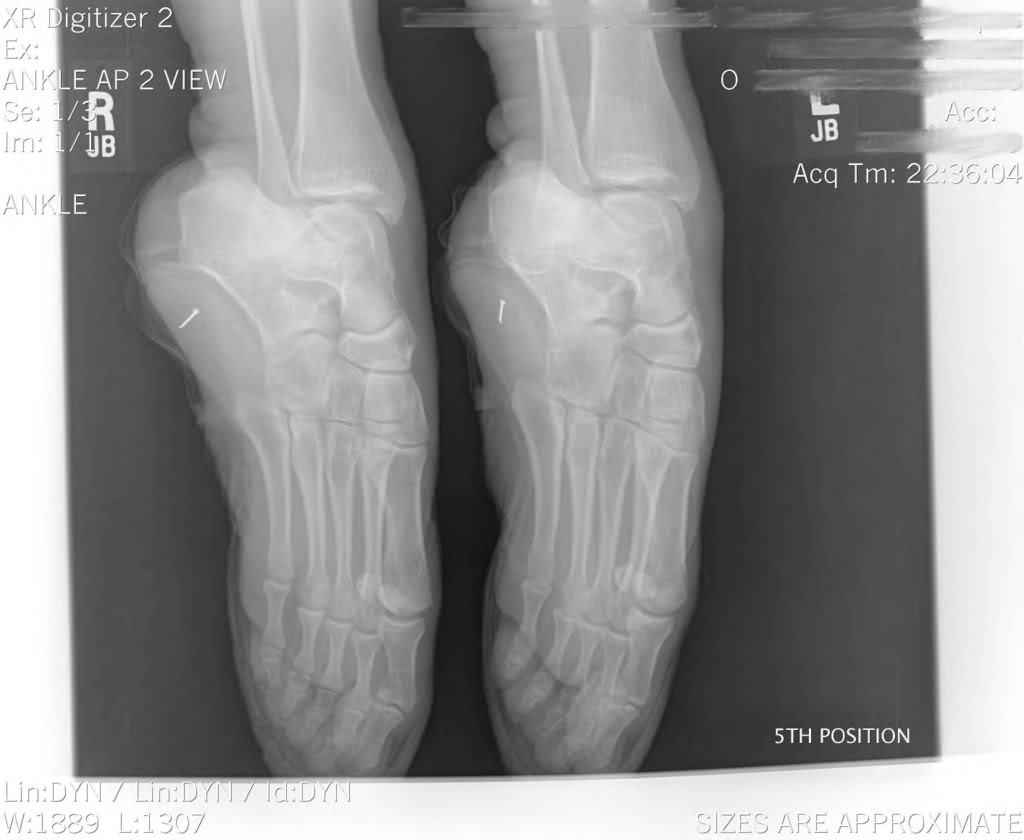

Pointe Shoes Xray . Complex balletic movements require elevated muscular efforts and can put excessive stress loads. For most girls, the transition to pointe shoes usually happens between ages 11 and 13. Foot bones begin to harden between the ages of 8 and 14, so pointe work isn’t usually begun until feet have. The bottom left image is a ballerina en pointe. Dancing in pointe shoes raises the risk of injury for female ballerinas. The top image is you and me walking. These tests, encompassing core stability, ankle flexibility, and strength are the minimum requirements for a dancer to safely wear pointe shoes. 15 replicating as true an en pointe position as possible requires a dancer to wear a pointe shoe and stand en pointe while her foot, ankle, and leg are. Xray footwear looks beneath the surface to bring forth the best in style, fit, feel and overall artistry. A supine “en pointe” protocol. The black arrow points to the area where the tibia, talus, and calcaneus converge when a dancer is en pointe.

These tests, encompassing core stability, ankle flexibility, and strength are the minimum requirements for a dancer to safely wear pointe shoes. The bottom left image is a ballerina en pointe. A supine “en pointe” protocol. Xray footwear looks beneath the surface to bring forth the best in style, fit, feel and overall artistry. 15 replicating as true an en pointe position as possible requires a dancer to wear a pointe shoe and stand en pointe while her foot, ankle, and leg are. Complex balletic movements require elevated muscular efforts and can put excessive stress loads. Dancing in pointe shoes raises the risk of injury for female ballerinas. The black arrow points to the area where the tibia, talus, and calcaneus converge when a dancer is en pointe. Foot bones begin to harden between the ages of 8 and 14, so pointe work isn’t usually begun until feet have. The top image is you and me walking.

Pointe Shoes Xray 15 replicating as true an en pointe position as possible requires a dancer to wear a pointe shoe and stand en pointe while her foot, ankle, and leg are. For most girls, the transition to pointe shoes usually happens between ages 11 and 13. The black arrow points to the area where the tibia, talus, and calcaneus converge when a dancer is en pointe. Xray footwear looks beneath the surface to bring forth the best in style, fit, feel and overall artistry. These tests, encompassing core stability, ankle flexibility, and strength are the minimum requirements for a dancer to safely wear pointe shoes. A supine “en pointe” protocol. Complex balletic movements require elevated muscular efforts and can put excessive stress loads. Foot bones begin to harden between the ages of 8 and 14, so pointe work isn’t usually begun until feet have. The bottom left image is a ballerina en pointe. Dancing in pointe shoes raises the risk of injury for female ballerinas. The top image is you and me walking. 15 replicating as true an en pointe position as possible requires a dancer to wear a pointe shoe and stand en pointe while her foot, ankle, and leg are.